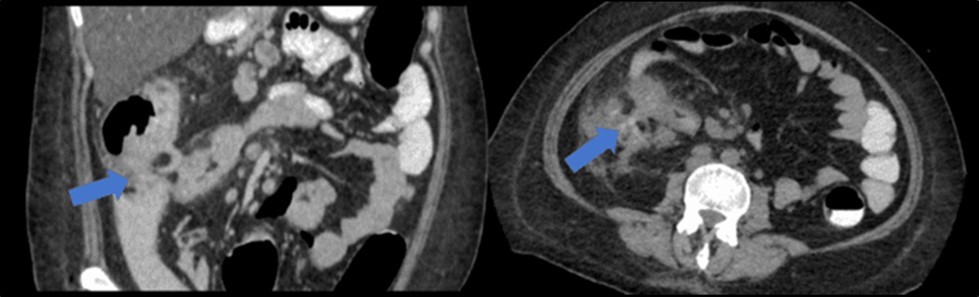

There was no evidence of malignancy or IBD seen during both endoscopic procedures. Computed tomography (CT) scan of the whole abdomen was done which showed inflammatory changes involving the cecum and adjacent duodenum and ileum with coloenteric fistulae. There was noted progression of abdominal lymphadenopathies as well as ascites. Main consideration was an infectious disease process (i.e. TB) (Figure 2, Figure 3, Figure 4 to Figure 5).

Figure 3.Coronal and axial view of the abdomen, the blue arrows pointing towards the suggestive communication to the ileum.